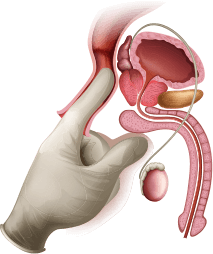

хирургических процедур

28573 мужчинам

специалистов

проверено